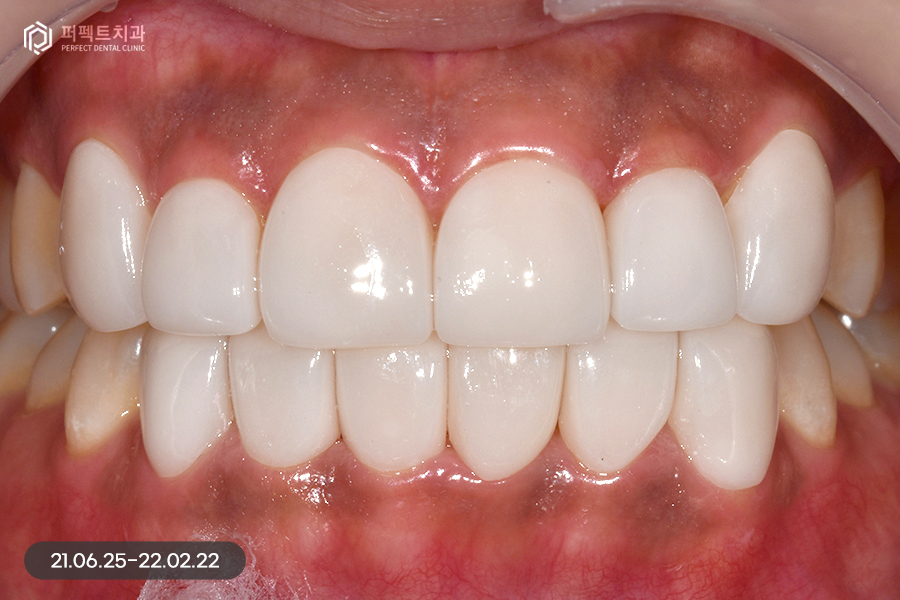

삭제 후 사진을 보시면 경계 부분만 0.1~0.2mm 정도 다듬어서 최소삭제로 진행을 하였습니다. 마취 없이 시술을 하였고 다듬은 후 임시치아를 하지 않아도 일상생활에 심미적으로 큰 불편감이 없었습니다.

색상은 환자분께서 직접 고르신 색상이고, 사진으로 보았을 때에는 많이 밝은 것처럼 보이지만 뒷 치아와 크게 어색하지 않으면서 환자분과 잘 어울리는 치아색상이었습니다.

치아를 0.10.2mm 정도 다듬은 후 0.20.3mm의 라미네이트를 부착하게 된다면 0.1~0.2mm 정도의 볼륨감이 생길 수 있는데 치아가 가지런한 상태에서 이 정도의 느낌 차이는 괜찮다고 볼 수 있습니다.